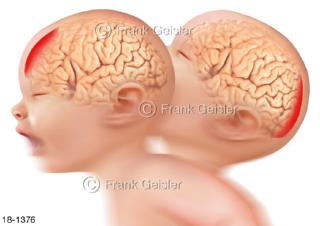

18-1376 Notfall Baby Kleinkind mit Schütteltrauma, Subduralhämatome Gehirn frontal dorsal